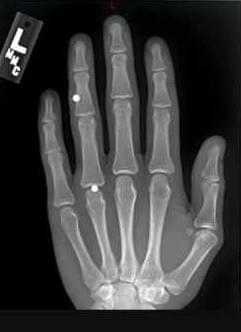

Инородные тела кисти

Инородными телами (ИТ) принято называть предметы, чужеродные для человеческого организма, внедряющиеся в органы, мягкие ткани, полости через естественные отверстия или поврежденные покровы. Инородными считаются также предметы, введенные в организм в процессе хирургического вмешательства с целью обеспечения здоровья пациента (протезы органов, сосудов или суставов, пластины, стержни, шовный материал).

Как показывает многолетняя практика хирурга, инородные тела чаще всего проникают в мягкие ткани кистей рук. Это могут быть иглы или их обломки, осколки стекла, металлическая стружка, щепки (занозы), пульки. Причинами проникновения инородных тел в ткани кисти являются травмы, полученные в быту или на производстве, чрезвычайные ситуации (аварии, теракты) или боевые действия.

По свидетельствам специалистов ИТ чаще всего локализуются в пястье, пальцах, реже - в запястье руки. При огнестрельных ранах ИТ рассеиваются по всей площади кисти.

Заподозрить присутствие ИТ возможно с помощью визуального осмотра и пальпации. В особых случаях назначается рентгенодиагностика, которая включает рентгенографию, рентгеноскопию, электрорентгенографию. Все ИТ классифицируются как рентген контрастные - видимые на снимке при рентгенографии, малоконтрастные - трудно определяемые на рентгеновском снимке, и рентген неконтрастные - не проявляющиеся при рентгенографии. Последние могут быть выявлены с помощью ультразвукового исследования.